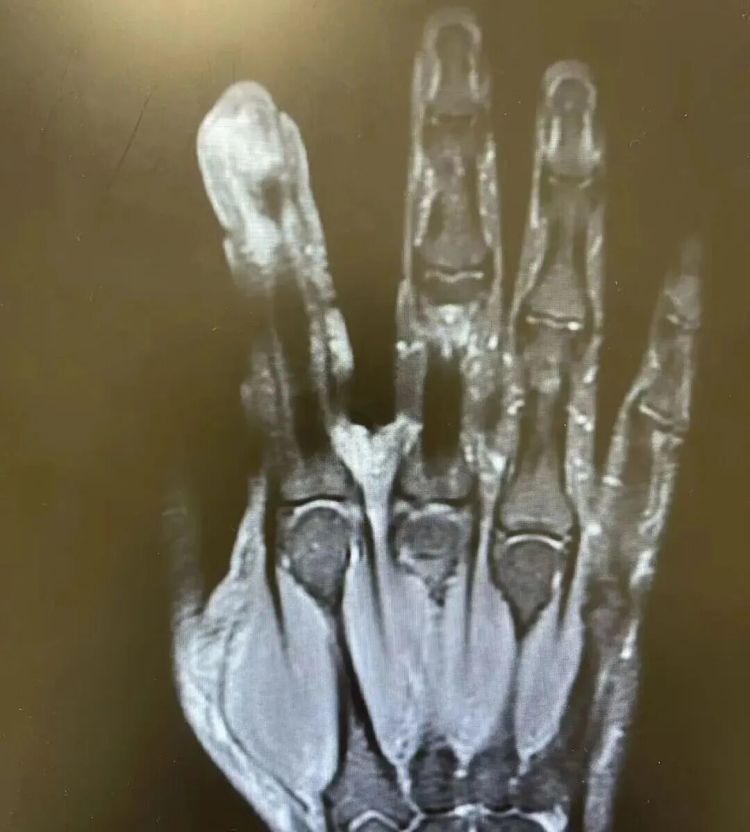

经检查,李大哥破溃的左手指尖严重感染,厌氧消化链球菌顺着破损处钻到骨头里,引发了严重骨髓炎。医生紧急手术,帮李大哥“刮掉”坏死的骨头碎片,清除了坏死的肌肉与皮肤。

图源:健康广东